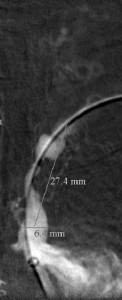

The 4 images you see above were recorded by me during primary stenting of irregular atherosclerotic stenosis of the left subclavian artery in a 54-year-old Hispanic female who was referred to my interventional radiology clinic for management of the stenosis. She had presented to her primary care physician with symptoms of hindbrain ischemia upon using her left upper limb and earlier workup confirmed left subclavian arterial stenosis. The 2 top images illustrate the character and severity of her disease, the first image in the bottom row shows the process of balloon-expandable stenting of the disease, while the 2nd image in the bottom row reveals complete elimination of the stenosis and reappearance of the left vertebral and internal mammary arteries, which were invisible on the pre-intervention angiograms reflecting the severity of the stenosis.